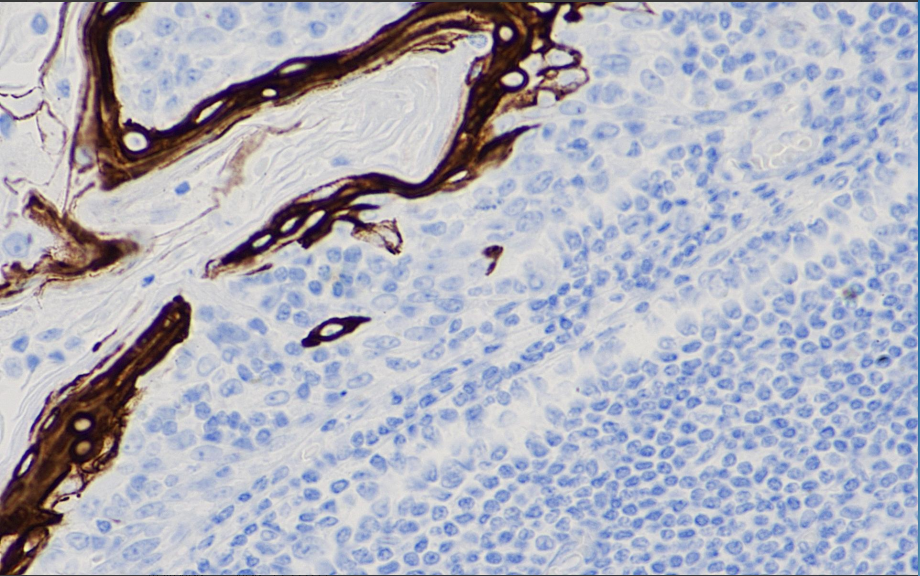

Positive control: tonsils

Cytokeratin 10 is a type I cytokeratin with a molecular weight of 56.5 kD, expressed in cells above the basal layer of stratified epithelium and keratinized epithelium. The expression of CK10 is associated with the maturation of malignant keratinocytes.

CK10 antibody reagents can specifically bind to CK10 molecular antigens. Immunohistochemistry kits containing CK10 antibody reagents are suitable for the auxiliary diagnosis of squamous cell carcinoma.